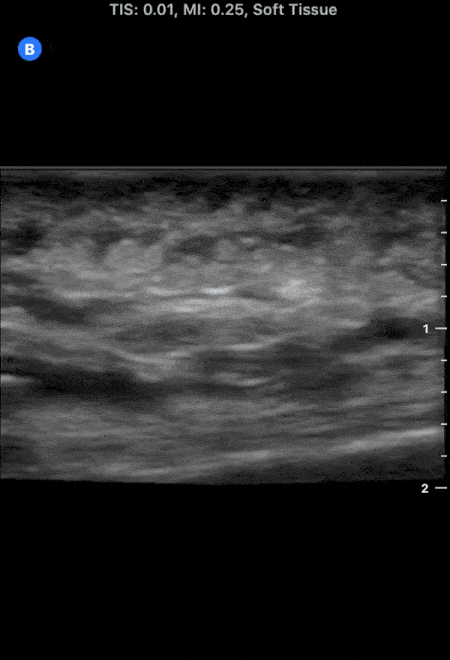

This image demonstrates the common finding of cobblestoning seen in cellulitis. Note the anechoic areas surrounding islands of subcutaneous tissue. Michael Macias, MD